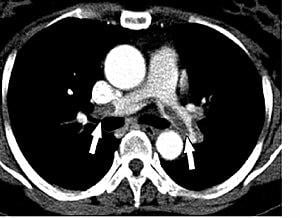

綜合《九派新聞》等媒體報道,福建中醫藥大學附屬人民醫院副院長、重症醫學科主任醫師李瑋解釋,經濟艙座位空間有限,乘客在狹小空間內長時間保持同一姿勢,活動範圍受限,血流速度自然減慢甚至淤滯,就容易形成血栓。李瑋指出,研究表明,連續飛行5、6小時以上,血栓的形成風險顯著增加;若肺部細小血管被栓塞,患者會感到呼吸困難、胸痛,若肺動脈被堵塞,則可能突發致命的肺栓塞,且症狀可能毫無預兆。

有報道引述中山醫院血管外科主任李昭輝表示,乘長途車或長時間乘坐飛機時,乘客如果吃安眠藥或大量喝酒,更容易導致長時間靜坐,患靜脈血栓的危險性更大。老人、服用避孕藥避孕的婦女、體重過重和剛做完手術的人是「經濟艙綜合症」的高發人群。李昭輝建議,首先靜坐1個小時應該活動幾分鐘,其次要注意多喝水,缺少水分會使血液變得黏稠,加速血栓形成。此外,檸檬汁可以促進血液循環;三高和肥胖人群,可服用阿士匹靈來預防血栓形成;旅客還可以穿醫用彈力襪來防靜脈血栓。